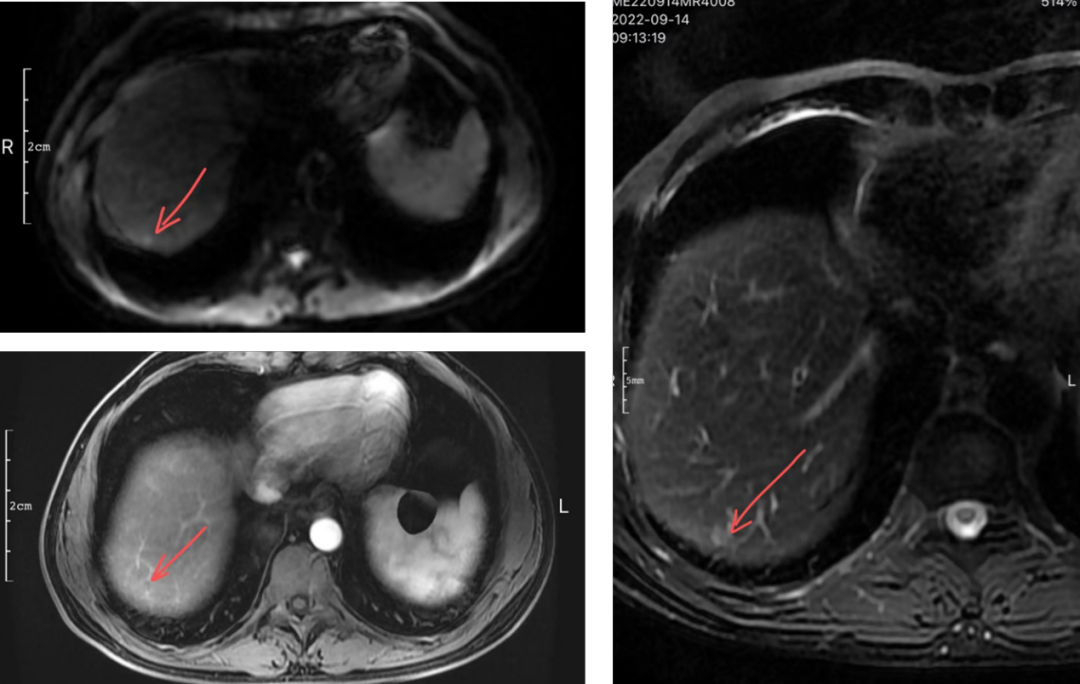

在全球,结直肠癌是发病率位居第三位、病死率位居第二位的肿瘤。肠镜筛查的普及以及手术方式的提升显著降低了结直肠癌的死亡率,但仍有一部分患者在初诊时已发展为晚期,失去手术根治的机会,且预后较差,5年生存率仅12%。许多转移性结直肠癌(mCRC)患者在经历一线治疗后,面临无药可用的困境。近年来,随着靶免联合治疗在系统治疗中逐渐前移,各种靶向治疗药物在mCRC的诊疗中也越发举足轻重。本文分享2例晚期结肠癌患者的诊疗经过,呈现瑞戈非尼在二线治疗为患者带来长生存的治疗价值及其良好的后线应用前景,以期为临床医生提供诊疗借鉴。 病例提供:海军军医大学附属长征医院 王湛 王湛 病例基本情况 一般信息:女 ,58岁。2020年10月,患者无明显诱因出现腹胀,无伴随症状,未予重视。后腹胀进行性加重,2020年11月中旬下腹部隐痛,与进食及体位变化无关,无肩背部放射痛。 辅助检查: 腹部超声:腹腔积液。 腹水脱落细胞病理:腺癌。 腹部增强CT:结肠肝曲癌;腹盆腔积液,腹盆腔腹膜多发转移。 结肠镜(2020-12-4):升结肠近肝曲见隆起型新生物,范围约4cm,新生物表面分叶状,质脆,触之易出血。肠腔狭窄,内镜尚可通过。 2020-12-8病理:横结肠,中分化腺癌,含部分粘液腺癌。 一线治疗2020-12-03至2021-02-24 CAPEOX+贝伐珠单抗 治疗4周期 病情进展,腹胀、腹痛加重,腹水增加。 2021-3-31 PET-CT:腹腔内及腹膜、脾脏、纵隔及右侧心膈角区、左侧锁骨区多发代谢增高灶,结合病史,考虑转移;双肺转移;腹腔及盆腔积液;结肠显示欠清,请结合肠镜检查;双侧胸腔少量积液,左肺下叶部分不张;双肺少许慢性炎症;右肝血管瘤;左肾结石。;子宫术后,痔疮可能;脊柱退变,腰3不稳,腰3/4、4/5、腰5/骶1椎间盘突出。 PFS:3个月 2021-4-6,完善基因检测(腹水标本):KRAS/APC/TERT/TP53/ target=_blank class=infotextkey>P53 突变,TMB 7.98/Mb,MSS 二线治疗,2021-04-02至2021-12 2021-3-31 2021-6-2 2021-8-6肠镜:结肠镜顺利插至回盲部,回盲瓣呈唇状。结直肠粘膜呈桔红色,光滑湿润,有光泽。血管纹理呈树枝状,清晰可见。 PFS:8月 三线治疗,2021-12-13至2022-01-23 三氧化二砷 2021-6-2 2021-11-22 2021-11-22 2022-2-8 PFS:2月 四线治疗,2022-02-10 化疗+免疫+瑞戈非尼+三氧化二砷 2022-2-10开始使用小剂量化疗(雷替曲塞+奥沙利铂+伊立替康)+免疫(信迪利单抗)+瑞戈非尼+三氧化二砷治疗。 疗效评估(2022-9-20):患者病情再次取得缓解。 2022-9-22至今采用维持治疗,降低治疗强度:雷替曲塞 +信迪利单抗+瑞戈非尼+三氧化二砷 2022-9-20 2023-2-8 PFS:13个月+ 该患者为中年女性,诊断为晚期多发转移性结肠癌,基因检测提示KRAS突变,BRAF、NRAS野生型,微卫星稳定,无法进行根治性切除。一线治疗加予CAPEOX联合贝伐珠单抗,治疗4周期后出现病情进展,腹胀、腹痛加重,腹腔积液增加,二线采用瑞戈非尼联合免疫和化疗,患者耐受良好,1周期后腹胀明显缓解,全身状态、PET-CT、肠镜结果较之前明显改善,继续原方案治疗,PFS长达8月。二线治疗进展后完善基因检测,发现TP53 突变,经与患者充分沟通,三线治疗采用三氧化二砷,疗效不佳。四线治疗在三氧化二砷基础上加用瑞戈非尼+免疫+化疗,患者病情再次取得缓解,PFS 超过13个月。近年来,随着精准医学及靶向、免疫治疗的发展,mCRC的管理与治疗策略的制定也变得复杂,合理选择治疗手段、优化全程管理至关重要。本例患者经历了一线化疗联合免疫治疗后疾病出现快速进展,我们个体化地在二线治疗中应用瑞戈非尼联合方案,患者疾病得到控制,PFS 8个月。在四线治疗方案中,再次挑战瑞戈非尼,依然获得较好的疾病控制效果,目前PFS已超过13个月。基于CORRECT和CONCUR研究,瑞戈非尼用于mCRC三线治疗已积累大量临床数据,目前已成为mCRC三线标准治疗方案。此外,REGONIVO、REGOTORI以及RIN方案证实了瑞戈非尼联合免疫治疗MSS型肠癌取得更长的总生存期。一线治疗后疾病进展,能否将瑞戈非尼使用前移,在二线治疗中加用以进一步延长患者生存,以及前线已经暴露过瑞戈非尼,后线再次使用瑞戈非尼是否可行,仍待在临床研究中进一步证实。 02 病例分享二 病例提供:海军军医大学第一附属医院 王薇 王薇 病例基本情况 一般信息:男性,41岁。2020年10月8日,无明显诱因下出现便血,为鲜红色,伴肛门坠胀不适,无排便习惯改变,无腹胀,无消瘦。1997年因“胃溃疡”行胃部幽门切除术;2019年行混合痔手术。 辅助检查: CEA 3.4ng/ml,CA199 3.52u/ml。 当地医院肠镜(2020-11-20):(距肛缘8-10cm)可见粘膜不规则隆起,表面溃烂,易出血。 肠镜活检病理:(直肠)中分化腺癌。 盆腔MRI增强(2020-11-26):直肠中段癌,考虑mrT3N1Mx,MRF-,EMVI-。 肝脏MRI增强(2020-11-27):未见明显异常。 治疗经过 首次手术治疗2020-12-09 腹腔镜辅助直肠癌拖出式适形切除术+末端回肠造口术 术中探查:直肠下段肿物,质硬,未浸润浆膜层,周围系膜未见肿大淋巴结。肿瘤大小约4*4*2cm,占肠腔1/2周,系膜完整。 术后病理: 直肠溃疡型肿瘤大小4.5x3.5x1.5cm;中至低分化腺癌,部分为粘膜腺癌;浸润至外膜层; 癌结节( 3枚+)、脉管癌栓(+)、神经侵犯(+)、肿瘤出芽(+,PDC1级);上下切缘(-)、环周切缘(-)、吻合圈(-);周围淋巴结(2/6),直肠外膜淋巴结(2/4),最高群淋巴结(0/4); 基因分型:KRAS Exon-2 G12D突变,NRAS、BRAF、PIK3野生型;免疫组化:MSH2(+),MSH6(+),MLH1 (+),PMS2(+),pMMR;Ki-67 80%。 术后分期:pT3N2aMx IIIB期 术后辅助治疗(XELOX方案) XELOX方案化疗3周期; 拟行盆腔放疗50gy/25次,2021-03-25起放疗6次 术后复查 肝脏MRI增强(2021-03-27):肝脏多发结节,较前为新发,考虑肝内多发转移瘤 一线治疗,2021-04-22至2021-06-24 mXELIRI+贝伐珠单抗 治疗4周期 患者治疗后出现恶心呕吐,胃纳明显减退,Ⅱ°粒细胞下降,腹泻,脱发,轻度手足皮肤反应,手足冰凉,心悸。患者无法耐受继续治疗 维持治疗,2021-7-15至2021-8-26,卡培他滨+贝伐珠单抗,共计治疗3周期 肝脏MRI增强(2021-5-31、2021-8-24):肝右后叶上段7mm小结节灶,转移不除外,腹膜后稍大淋巴结较前相仿,随访。 2021-3-27与2021-5-31的肝脏MRI增强对比图 2021-8-24 肝脏MRI增强 盆腔MRI增强(2021-8-25):术区及骶前软组织肿胀,左侧条索影,结合CT考虑术区置管术后改变,较2021-06-01片大致相仿。 疗效评估:PR 后患者诉心悸、乏力、胃纳不佳;血压正常;心肌酶正常;心脏彩超LVEF 64%;EKG: 窦性心率,T波低平;尿蛋白(-)。患者对化疗非常抗拒。 二线治疗,2021-09-17至2021-12-15 盆腔MRI增强(2022-9-13):术区及骶前软组织肿胀,左侧条索影,结合CT考虑术区置管术后改变,较前片大致相仿。 胸部CT(2022-9-13): 右肺下小结节,随访。 疗效评估:PR。 2022-12-20肝脏MRI增强:平扫+增强未见明显异常。 2022-12-21盆腔MRI增强:直肠癌术后,盆腔区未见明显复发及转移病灶。 病例总结 该患者为中年男性,诊断为局部晚期直肠癌,原发灶术后分期IIIB期,基因检测KRASExon-2G12D突变、微卫星稳定。术后仅3月余在XELOX方案辅助化疗、盆腔放疗期间出现多发肝转移,疾病进展转移灶不可切除,进而接受XELIRI方案联合贝伐珠单抗二线全身治疗。治疗后肝脏多发转移瘤退缩理想,病灶明显缩小减少。但患者治疗副反应不可耐受,改卡培他滨联合贝伐单抗治疗后持续有效,但仍无法耐受副反应。遂予以瑞戈非尼靶向治疗:120mg日剂量口服,服用三周停用一周至今。患者耐受良好,近期复查未发现明显复发转移病灶。目前二线PFS已达23个月,瑞戈非尼二线维持治疗DoR17个月。目前,二线治疗在不同患者亚群的优选方案仍存在争议。而整个系统治疗到了三线阶段,标准治疗主要价值是能够延长患者的疾病控制时间,缩瘤效果和客观缓解率均不理想,并没有满足目前的治疗需求。根据目前的药物机制和临床研究结果,考虑到患者的具体情况:涵盖治疗目标、体质状况、对预估的不良事件的耐受性及是否存在相关危险因素、既往治疗用药情况等方面,我们采用了个体化的瑞戈非尼二线维持治疗方案取得良好疗效,这种治疗策略希望能在规范临床研究中证实。病例分享一